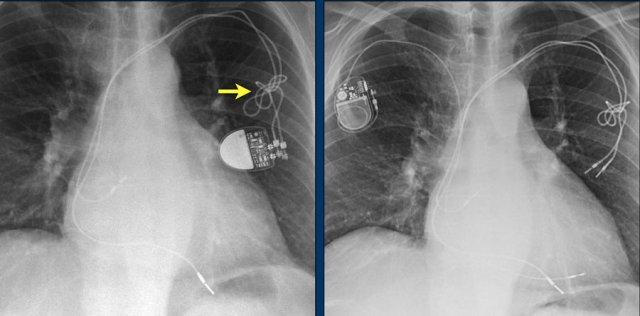

Đây là một bệnh nhân khác mắc hội chứng Twiddler.

Lưu ý hình ảnh điện cực bị cuộn xoắn gần máy tạo nhịp và tại đầu điện cực trong thất phải (mũi tên).